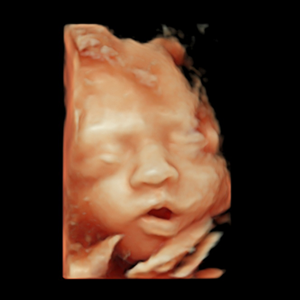

- Pionero en México en ofrecer diagnóstico por ultrasonido dentro del consultorio, así como en incorporar tecnología 3D y Doppler.